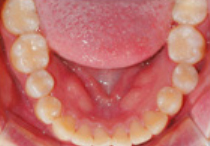

BEFORE

AFTER